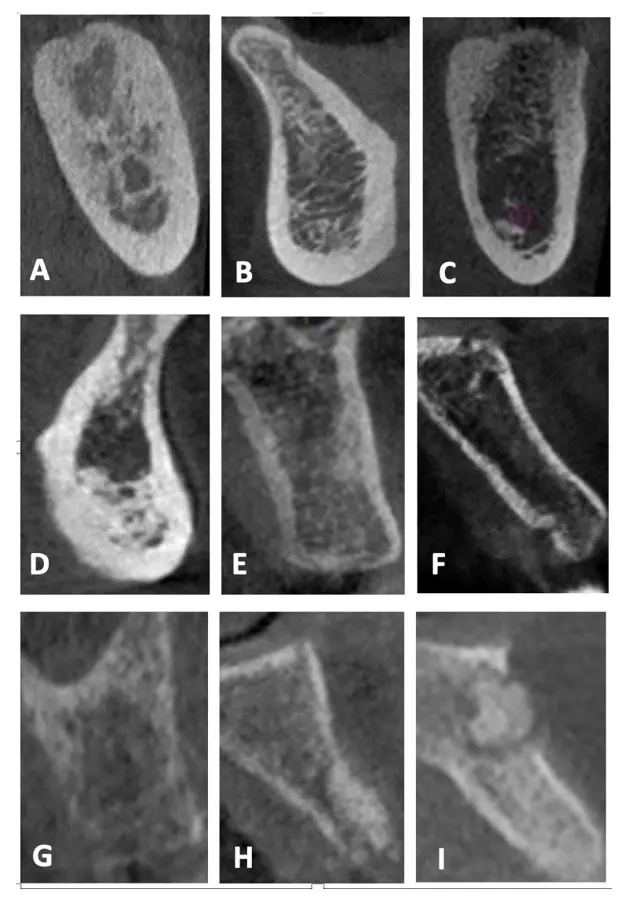

Cortes de la zona maxilar en los que se aprecia diferentes formación óseas como hueso cortical grueso y hueso esponjoso con espacios medulares amplios, cada una de las cuales requiere una indicación clínica específica.

Una reciente publicación de estudios con CBCT propone una modificación a lo anteriormente propuesto por Lekholm y Zarb, que permite sugerir su aplicabilidad para distinguir entre las diversas combinaciones de hueso cortical y esponjoso para definir adecuadamente el tratamiento a fin de optimizar los resultados.17 Esta propuesta se basa en la evaluación de la calidad ósea respecto al grosor de la cortical y a la visibilidad de la cantidad de trabéculas y el tamaño de los espacios medulares en el hueso esponjoso (Figura 4):

• Tipo I: Hueso cortical predominante que rodea al hueso esponjoso de cantidad escasa con trabéculas nítidas en toda la imagen y presencia de espacios medulares pequeños y visibles.

• Tipo II-A: Hueso cortical grueso que rodea al hueso esponjoso de cantidad abundante con trabéculas nítidas en toda la imagen y presencia de espacios medulares pequeños y visibles.

• Tipo II-B: Hueso cortical grueso que rodea al hueso esponjoso de cantidad abundante con predominio de trabéculas difusas en el hueso basal y presencia predominante de espacios medulares amplios y visibles.

• Tipo II-C: Hueso cortical grueso que rodea al hueso esponjoso de cantidad abundante con predominio de trabéculas muy gruesas y nítidas en la basal, con presencia de espacios medulares pequeños y visibles.

• Tipo III-A: Hueso cortical delgado que rodea al hueso esponjoso de cantidad abundante con trabéculas nítidas en toda la imagen y presencia de espacios medulares pequeños y visibles.

• Tipo III-B: Hueso cortical delgado que rodea al hueso esponjoso de cantidad abundante con predominio de trabéculas difusas y presencia de espacios medulares difusos.

• Tipo IV: Hueso cortical difuso que rodea al hueso esponjoso de cantidad abundante con predominio de trabéculas difusas y presencia de espacios medulares difusos.

• Tipo V: Hueso regenerado, de cantidad, visibilidad de las trabéculas y espacios medulares variables.

• Tipo VI: Hueso con patología, de cantidad, visibilidad de las trabéculas y espacios medulares variables.

Figura 4. Calidad ósea según la clasificación de Lekholm y Zarb modificada. A: Tipo I, B: Tipo II-A, C: Tipo II-B, D: Tipo II-C, E: Tipo III-A, F: Tipo III-B, G: Tipo IV, H: Tipo V, I: Tipo VI.